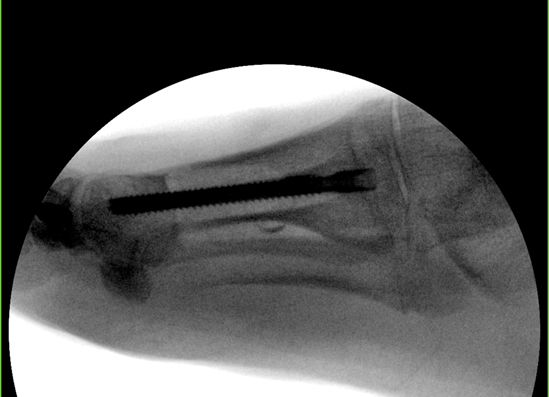

TOTAL ANKLE REPLACEMENT :: ORIF CALCANEUS :: ORIF ANKLE FRACTURE DISLOCATION :: COMPLEX BUNION AND LESSER TOE CORRECTION :: TALUS FRACTURE -1 :: TALUS FRACTURE -2 :: LISFRANC REPAIR :: COMPLEX TRIPLE ARTHRODESIS 1 :: COMPLEX TRIPLE ARTHRODESIS 2 :: MINIMALLY INVASIVE BUNION REPAIR 1 :: MINIMALLY INVASIVE BUNION REPAIR 2 :: ARTHROSCOPIC CARTILAGE REPAIR :: TENEX SPUR DEBRIDEMENT :: Haglunds Debridement and Achilles Repair